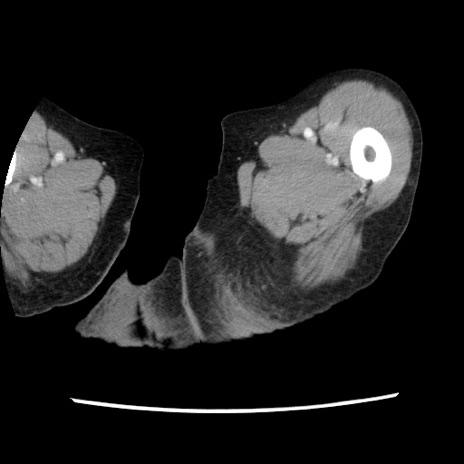

冠状断像